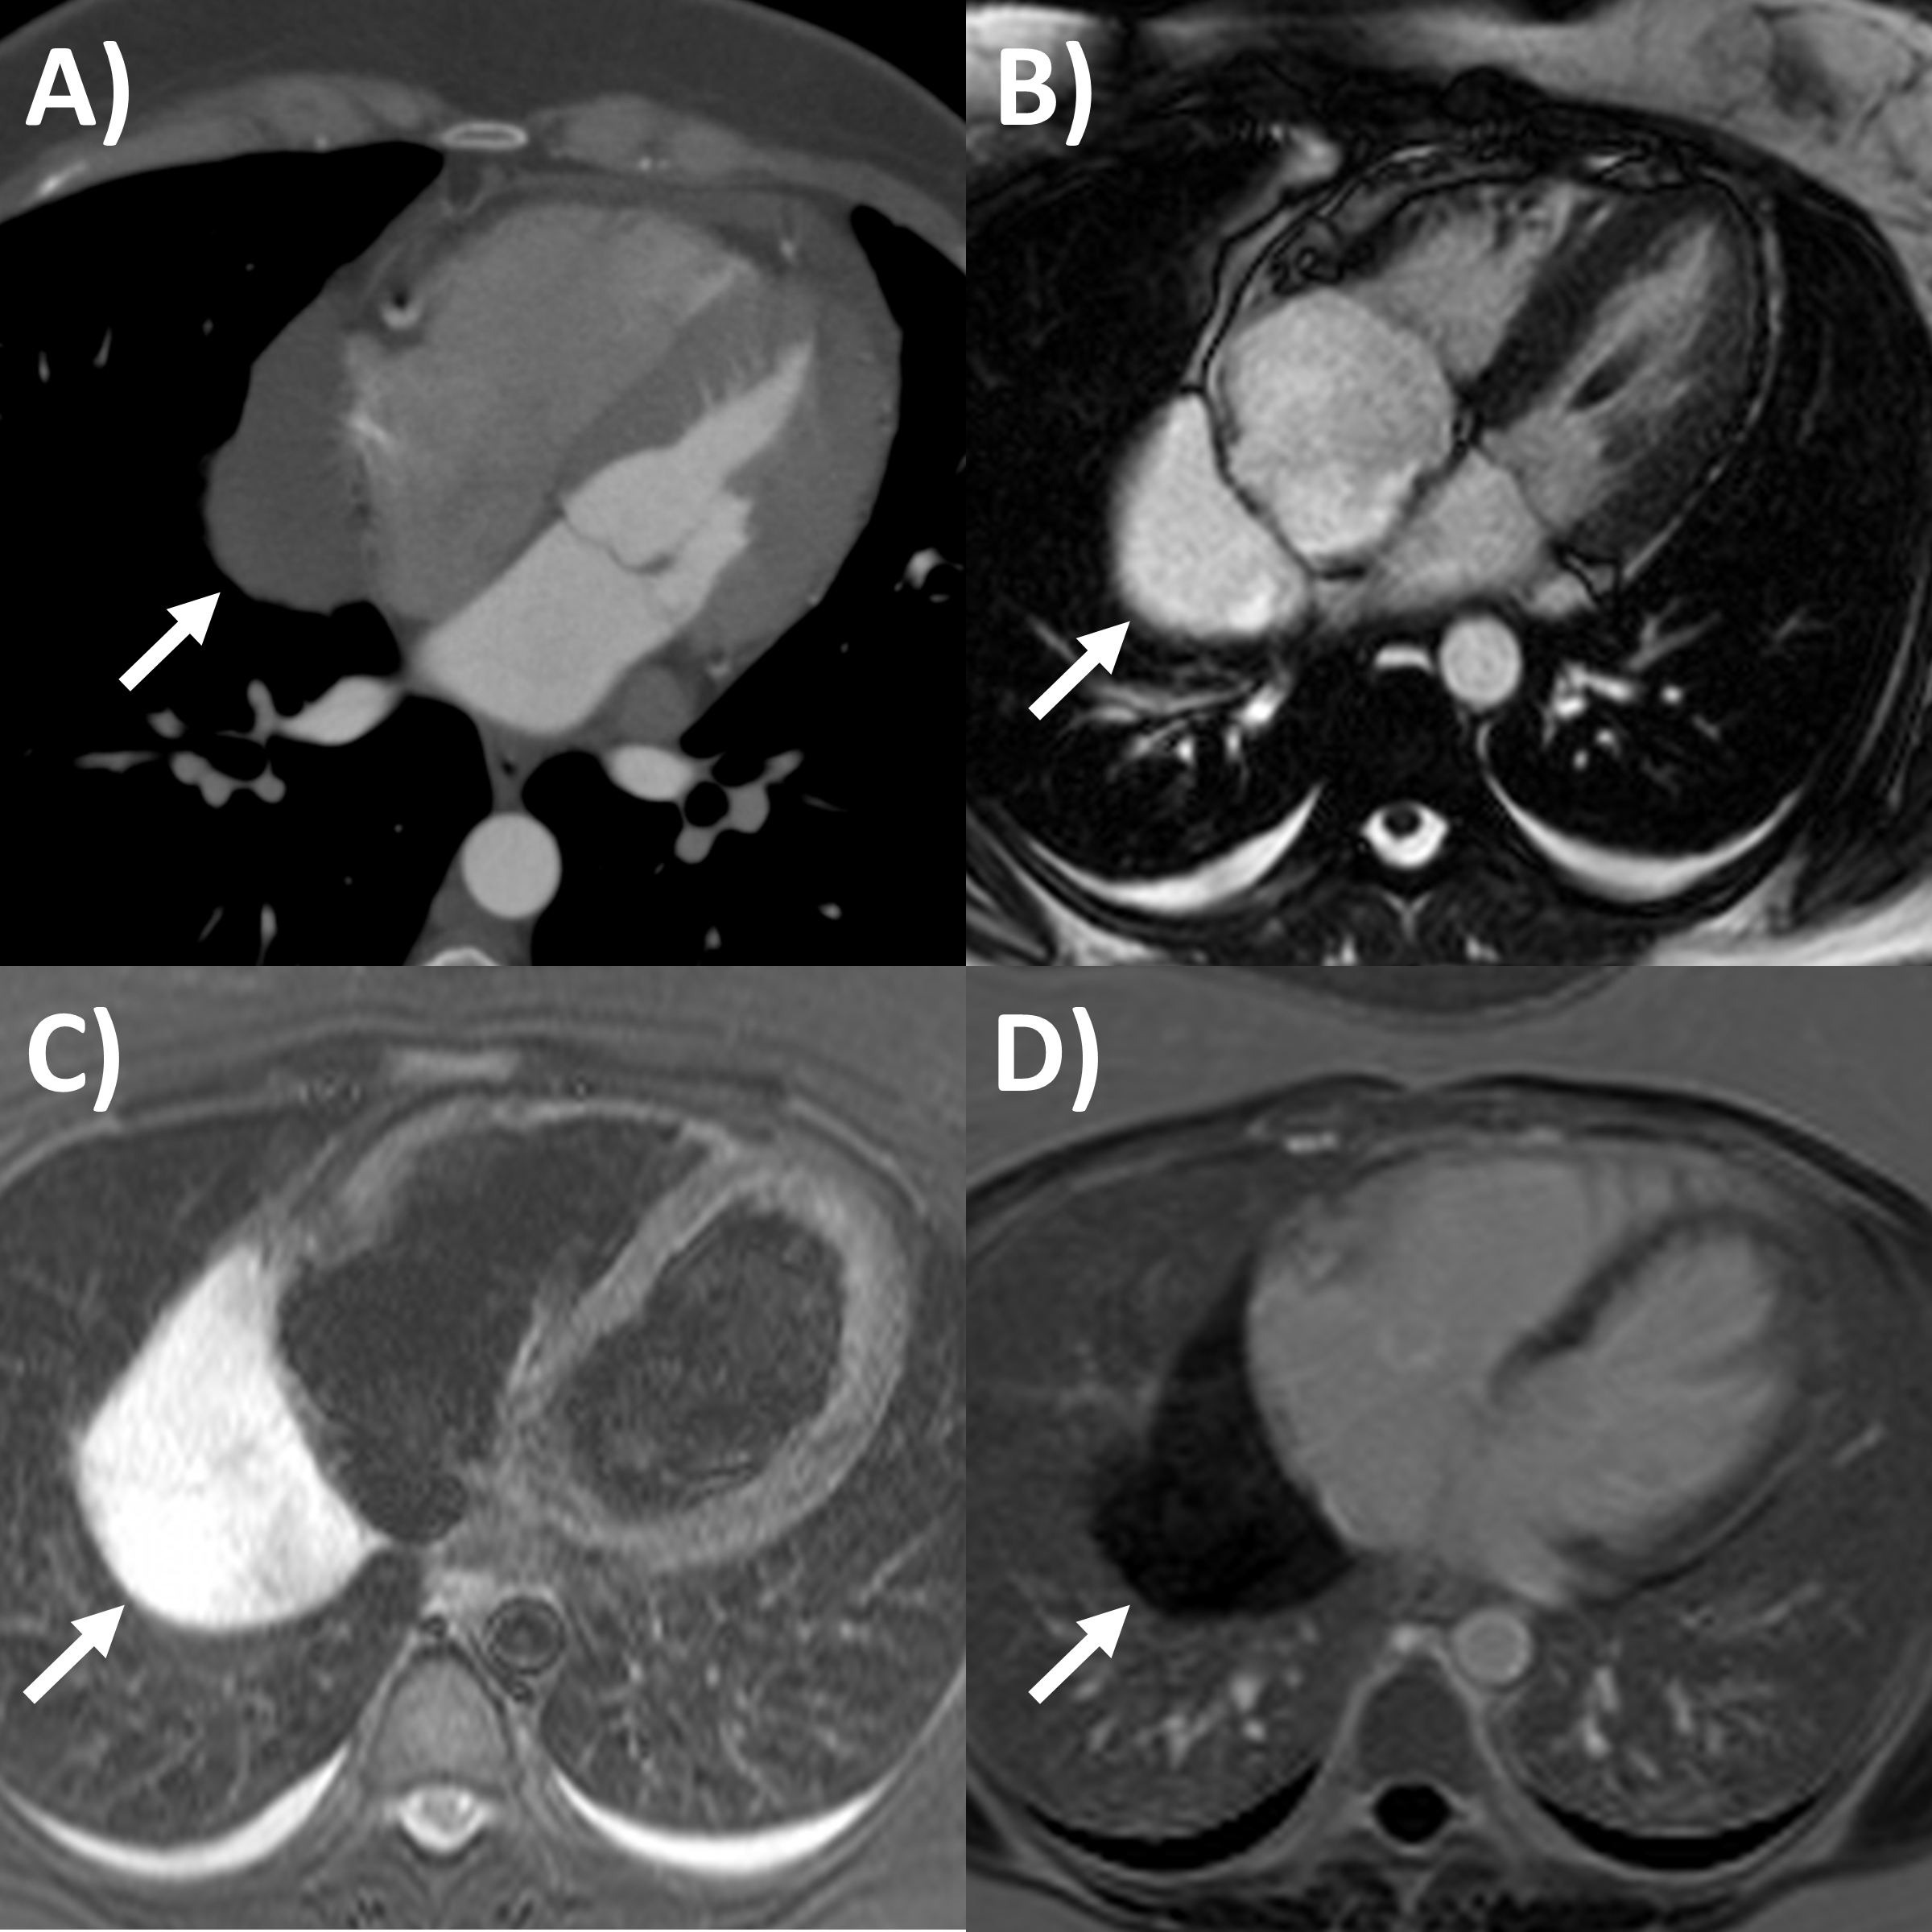

It is critical for cardiology clinicians to be familiar with echocardiographic

features that may be seen in pericardial tamponade, despite it ultimately being a

clinical diagnosis incorporating signs of hemodynamic compromise [2]. The main

echocardiographic criteria according to guidelines (Fig. 2) include dilated

inferior vena cava with minimal (

Fig. 2.Echocardiography evaluation of pericardial tamponade. (A)

Dilated inferior vena cava (2.7 cm) with minimal